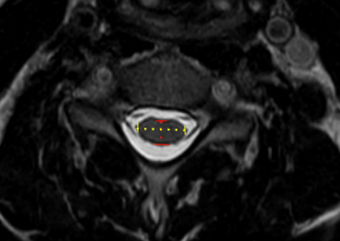

Image Type Cervical Spine X-Ray CT Scan MRI Scan Compression Ratio (AP diameter transverse diameter of cord) Cord Cross-Sectional Area (CSA) Cross-Sectional Canal Area Maximum Spinal Cord Compression Pavlov/Torg (Canal-Body Ratio) Sagittal Canal Diameter Spinal Cord Signal Change - T1 Hypointensity Spinal Cord Signal Change - T2 Hyperintensity (+ number of levels)